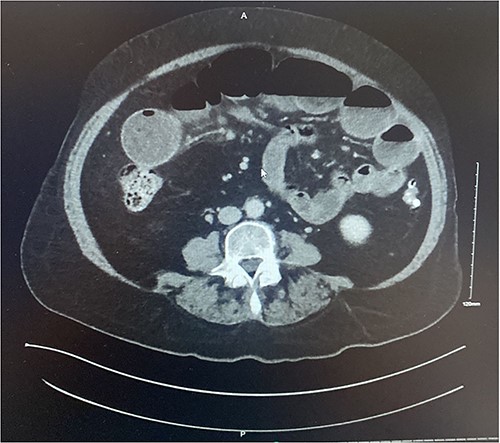

A 73-year-old female presented complaining of acute onset right sided upper abdominal pain associated with three episodes of bilious vomitus and constipation. Clinically, her abdomen was tender, distended, and tympanic with increased bowel sounds. Of note, she described a 3-month history of repeated low grade abdominal pain with vomiting. The clinical picture was concerning for that of bowel obstruction. Contrast enhanced CT scan of the abdomen and pelvis (CTAP) demonstrated multiple dilated loops of small bowel measuring 4.5 cm at their maximum calibre. In the right abdomen there was a focus of ileo-ileal intussusception with a filling defect measuring ~6–7 cm (Figs 1–2). Multiple enlarged enhancing lymph nodes, measuring up to 10 mm, were identified at the level of the intussusception. The duodenum, distal ileum, and jejunum were collapsed.

Axial section of contrast enhanced CT AP demonstrating intussusception with surrounding lymphadenopathy.